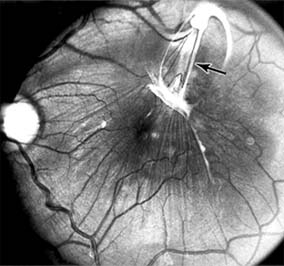

Presumed Ocular Histoplasmosis Syndrome (Figures 10-5, 10-6 and 10-7)

In this disease, serous and hemorrhagic detachments of the macula are associated with multiple peripheral atrophic chorioretinal scars and peripapillary chorioretinal scarring (see Chapter 7). The syndrome usually occurs in healthy patients between the third and sixth decades of life, and the scars are probably caused by an antecedent subclinical systemic infection with Histoplasma capsulatum. The macular detachments are due to subretinal neovascularization, and the visual prognosis depends on the proximity of the neovascular membrane to the center of the fovea. If the membrane extends inside the foveal avascular zone, only 15% of eyes will retain 20/40 vision. A macular scar may change over time, and 10% of patients with normal maculae will develop new atrophic scars in this region. The relative risk of developing macular subretinal neovascularization in the second eye of an affected patient is significant, and these patients should be instructed in the frequent use of the Amsler grid and the importance of prompt examination when changes are detected.

Figure 10-5

Figure 10-5: Presumed ocular histoplasmosis syndrome with active disease (large arrows) and an inactive pigmented macular scar (small arrow). Peripapillary pigmentation (curved arrow) is also present.

Figure 10-6

Figure 10-6: The early fluorescein angiogram shows an inactive hypofluorescent scar (small arrow) and the characteristic lacy hyperfluorescence of subretinal neovascularization (open arrows).

Figure 10-7

Figure 10-7: Late fluorescein leakage from macular subretinal neovascularization in a patient with presumed ocular histoplasmosis syndrome.